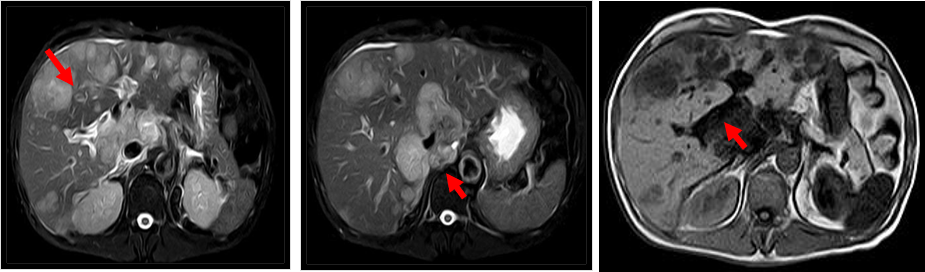

患者男性,51岁,因“上腹隐痛不适3月余,加重1月”于2019年2月23 日入院。既往 “糖尿病”史2年,现血糖控制尚可;饮酒史20余年,每周3~4次,半斤/次;吸烟史:20支/天×20余年。体格检查:皮肤巩膜无黄染,前胸可见数颗蜘蛛痣,心肺查体无阳性体征;右肋沿下3cm可及肿大肝脏,未及腹部包块。实验室检查:癌胚抗原(CEA)6.60 ng/ml,甲胎蛋白(AFP)2.20 ng/ml,HBsAg (-),HBsAb (+),HBeAg (-),HBeAb (-),HBcAb (+),Anti-HCV (-)。入院时肝脏MRI检查示:肝内多发占位性病变,大小不一,T1WI病变呈低信号,T2WI病变呈高信号,内部信号不均匀;门静脉右支见充盈缺损,考虑癌栓(图1)。2019年2月26日行右肝肿物穿刺活检术,病理示“倾向低分化肝细胞癌”。初步诊断:肝细胞性肝癌Ⅲa期,BCLC C期;门脉右支癌栓(Vp3型,程氏Ⅱ型);肝功能Child-pugh A级。

图1. 2019年2月23日入院时MRI检查